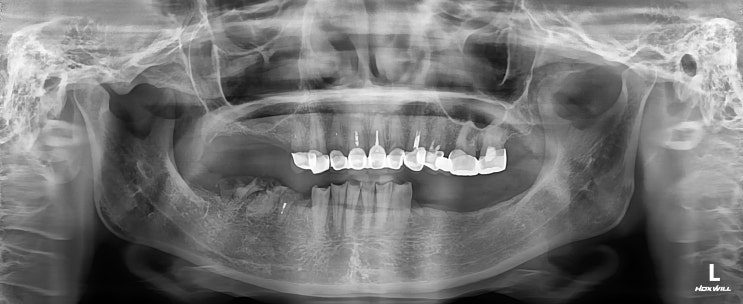

[수서역치과] 망가진 임플란트 재식립

안녕하세요 매서운 한파가 치는 2월입니다 해외나가셨다가 다시 오신 환자분이신데 예전에 진료받은 케이스...